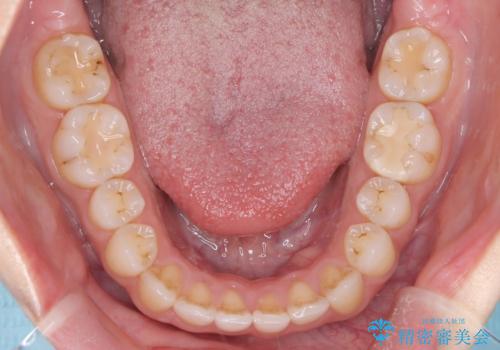

【オープンバイト】前歯のがたがたをなおしたい。

- 笑った時の前歯の見た目が気になることを主訴に来院されました。

上の歯が下の前歯を少し隠すぐらいを目指し、インビザラインにて治療を行いました。

オープンバイトの後戻りを防ぐためには舌のトレーニングが必要です。